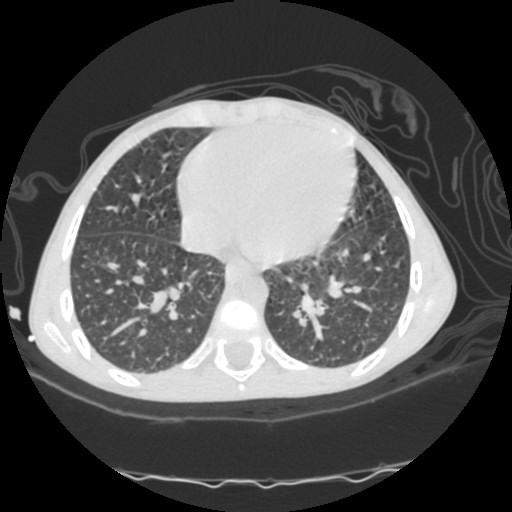

- Computerized tomography (CT) of chest.

| CT3 | CT4 | CT5 |

| CT1 | CT2 |